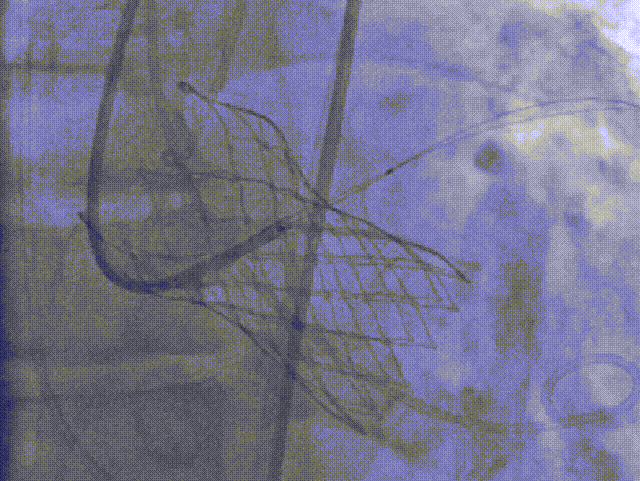

术者采用患者右侧主入路,顺利完成导丝和猪尾跨瓣等准备工作。进Landerquist超硬导丝,采用25mm球囊进行预扩,仔细评估冠脉风险后,决定对冠脉采取保护措施。根据球囊扩张情况,术中决定使用金仕生物的ProStyle预装干瓣TAV32。打开包装后,很迅速的完成了瓣膜和系统植入前的准备。输送过程系统和瓣膜轻松过弓并顺利跨瓣;开始初步释放,然后快速起搏下释放,发现位置略高后进行回收,重新定位后最终成功完成释放。反复造影发现冠脉存在阻塞风险,武汉协和团队按照风险预案在左冠植入4.0*18mm支架进行保护。术后显示左右冠脉血液灌注通畅,术后超声测量峰值流速1.45m/s,峰值压差8mmHg,几乎无瓣周漏。入路闭合顺利,无心脏及血管并发症,手术成功。

再回收后释放,术中冠脉评估